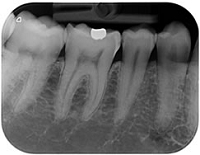

デジタルレントゲンシステム ・ デンタル&パノラマ

従来の単純撮影法X線システムには必ず現像という工程が必要であるため、常に一定の条件で撮影した画像を見ることはできませんでした。

これをデジタル化することにより、常に一定の条件で精細な画像を見ることが出来るようになるばかりではなく、放射線による被曝線量も1/10程度まで減少させることが可能になりました。